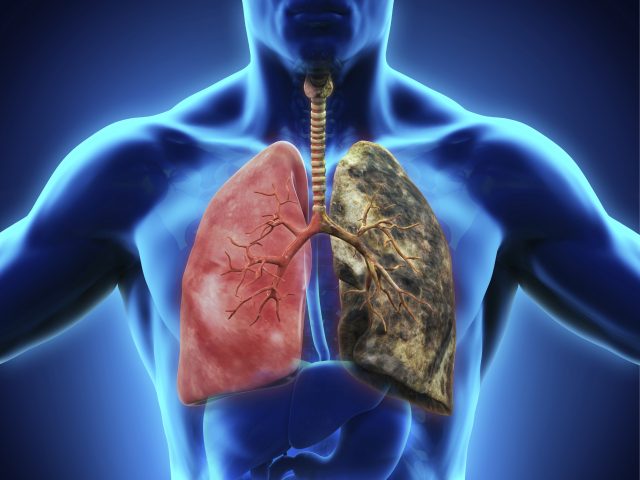

Lima, 7 de abril de 2023.- En el marco del Día Mundial de la Salud, fecha que se celebra en el Perú cada 7 de abril, muchos buscan crear conciencia acerca de las diversas enfermedades que padecen los peruanos e incluso, la población a nivel mundial. Una de estas que ha venido tomando fuerza en los últimos años, es el Cáncer de Pulmón, puesto que, en la actualidad, cerca de 3000 peruanos fallecen por esta enfermedad, y, según la OMS, es una de las principales causas de muerte en todo el mundo.

“A nivel mundial, en hombres, el Cáncer de Pulmón es considerado con el 18% de los casos, el cáncer más mortal. Sin embargo, en las mujeres, este también podría llegar a ser igual de peligroso, ya que se encuentra con un 12.3% de casos, seguido del de seno que se lleva un 13.2%.”, comentó el Dr. Hugo Caballero, Neumólogo y Ex Presidente de la Asociación Colombiana de Neumología y Cirugía de Tórax.

“Existen muchos factores que pueden aumentar el riesgo de desarrollar este tipo de cáncer; sin embargo, debemos de tener en cuenta que esta enfermedad se relaciona en un 90% con el consumo de cigarrillo, así como también debemos de saber que, consumir este producto, puede también, producir cáncer en labios, boca, laringe, esófago, estómago, páncreas, hígado, colon y recto, riñones, uréteres, vejiga y cuello uterino”, comentó el Dr. Caballero. “Hay muchas alternativas para intentar que una persona deje de fumar y una de ellas puede ser el uso de cigarrillos electrónicos o vapes, puesto que, en realidad lo peligroso de fumar no es la nicotina, sino los más de 7000 compuestos químicos que se pueden encontrar en un cigarrillo.”, agrega.